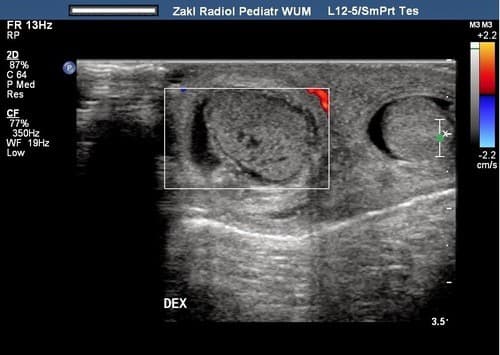

Siêu âm là một trong những phương pháp giúp phát hiện sớm ung thư tinh hoàn

- Siêu âm bìu: Phương pháp này giúp phát hiện tới 75% các trường hợp khối u hoặc tràn dịch màng tinh hoàn.